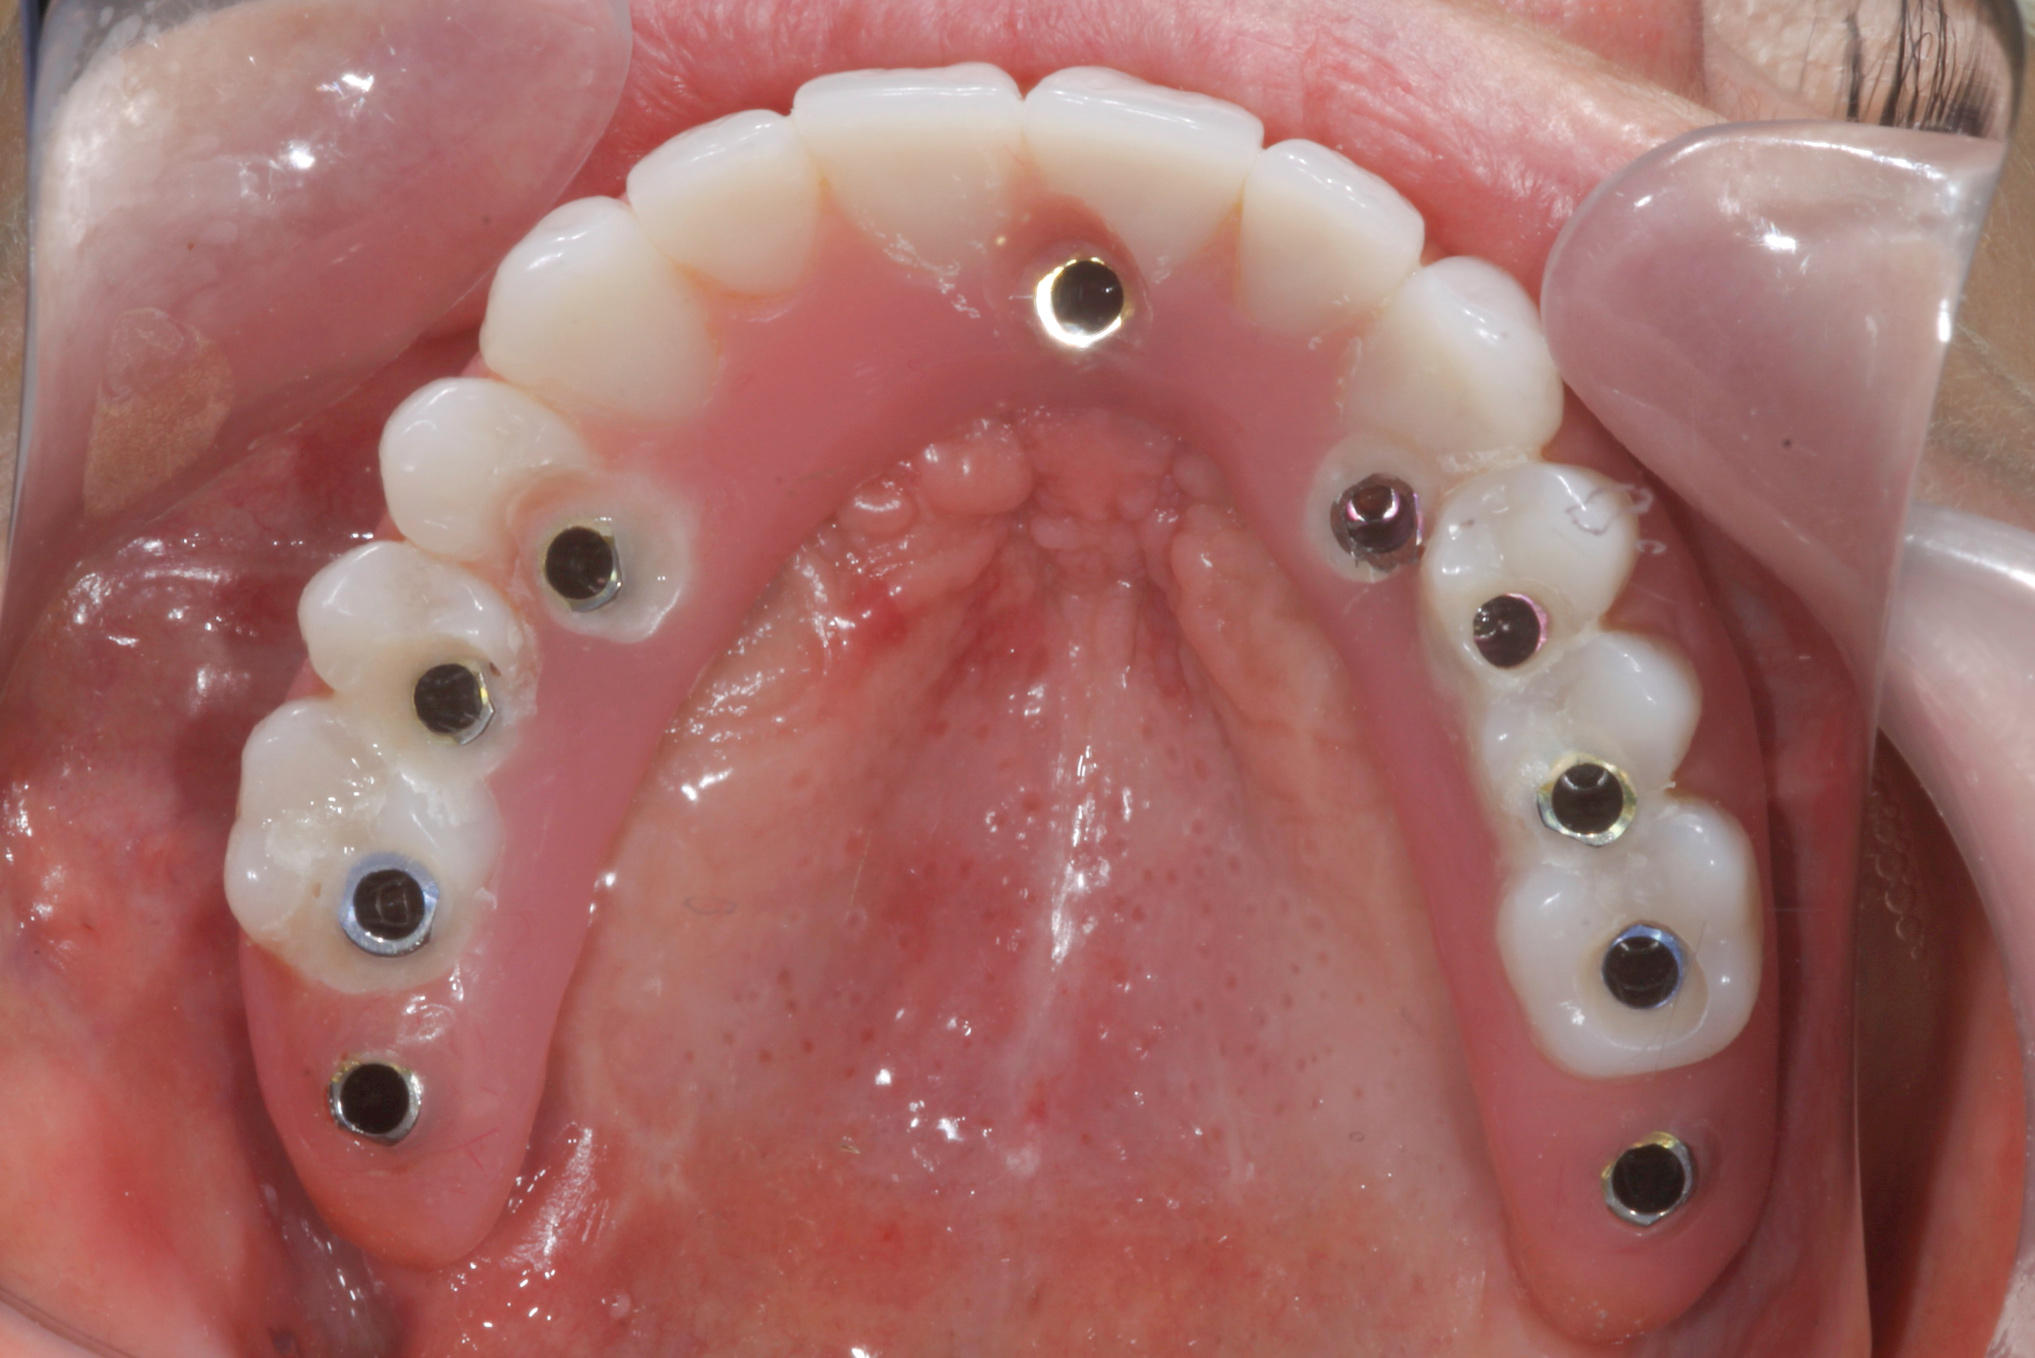

Fig 12. Immediate insertion of provisional restoration.

Figure 12